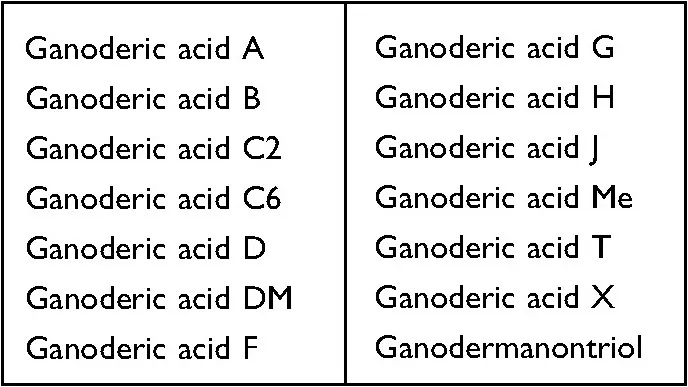

In the end of this study, the analysis of the “molecular docking simulation system” found that at least 14 ganoderic acids in the triterpenes of Ganoderma lucidum (as shown in the table below) can directly and effectively bind to the key cytokine HMGB-1, thus inactivating the pro-inflammatory activity of HMGB-1.

Since anti-inflammation is one of the important mechanisms of Ganoderma lucidum to reduce Cisplatin-induced hepatotoxicity, “richness in Ganoderic acid” has become an indicator component of Ganoderma lucidum to protect the liver.

What kind of Ganoderma lucidum ingredients can contain such abundant Ganoderic acids? According to past research, it is known that they are mainly present in the “Ganoderma lucidum fruiting body alcohol extract”.